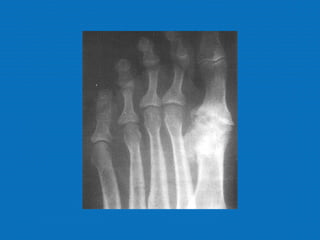

RADIOLOGIA

No início da doença não se observam anormalidades. Com seu

desenvolvimento, observam-se:

• Diminuição do espaço intra-articular

• Esclerose subcondral (eburnação)

• Osteófitos;

• Erosão e anquilose óssea (pseudocistos ósseos).

RADIOLOGIA No início dadoença não se observam anormalidades. Com seu desenvolvimento, observam-se: • Diminuição do espaço intra-articular • Esclerose subcondral (eburnação) • Osteófitos; • Erosão e anquilose óssea (pseudocistos ósseos).